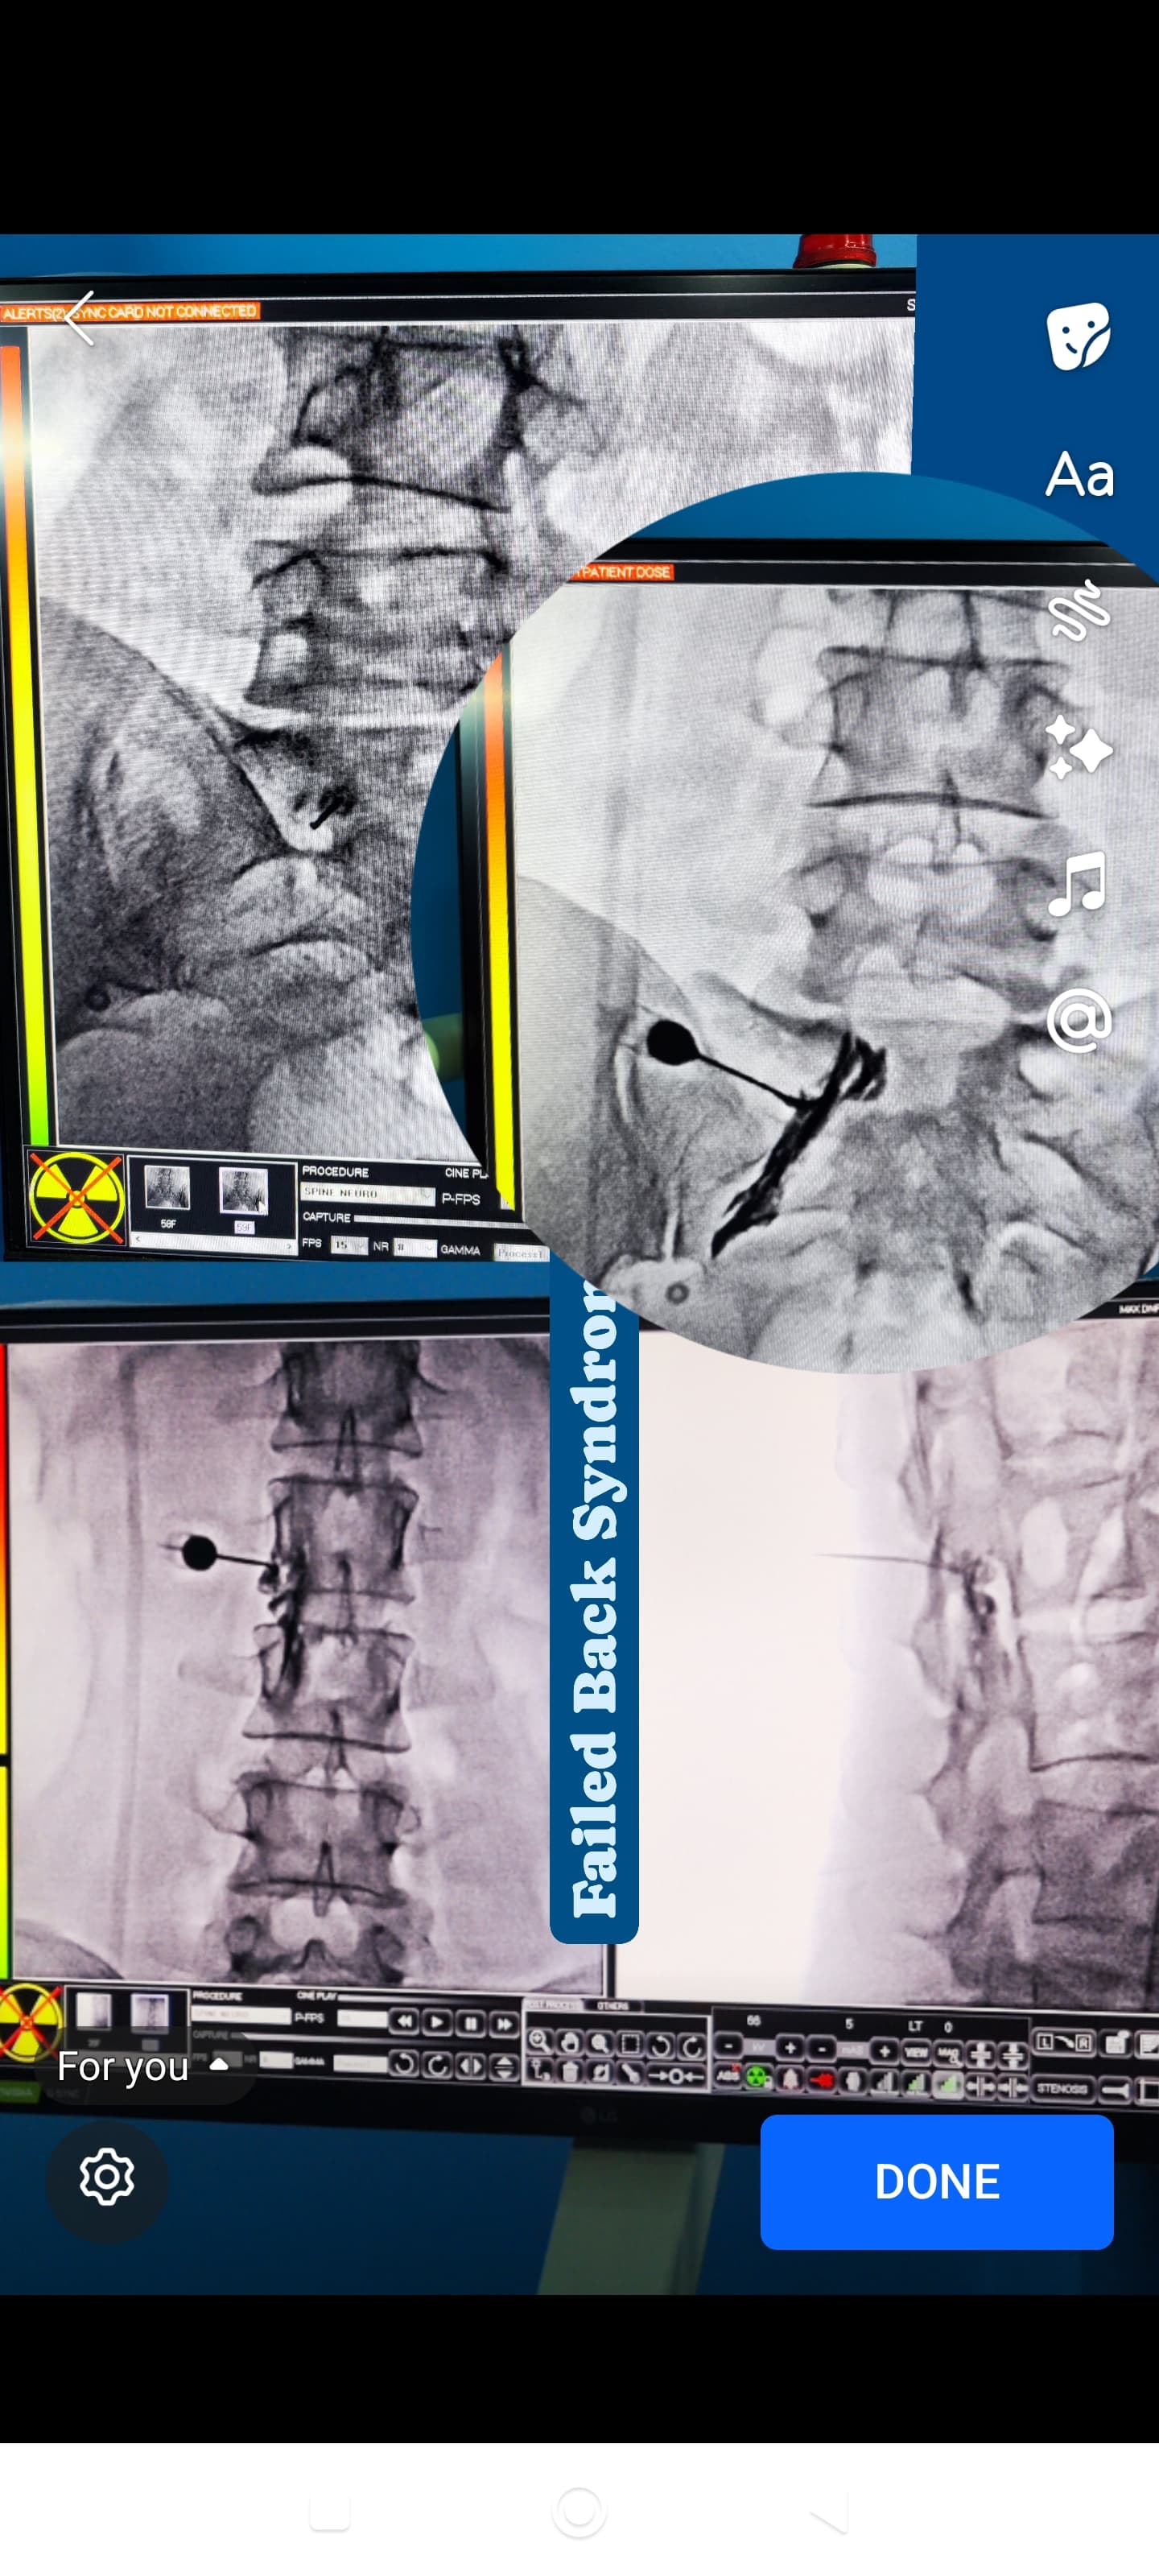

Glimpses of Advance Pain Care

Step inside our clinic and see our commitment to a healing environment and advanced care.